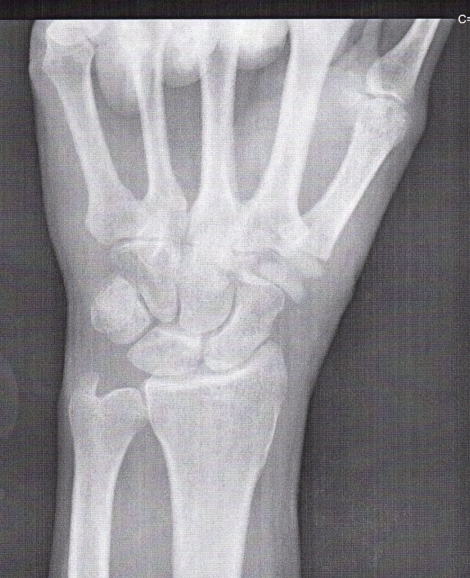

Here's a post-surgery x-ray. The trapezium was removed and replaced with a flexible plastic (maybe nylon or some other appropriate material) appliance. It has a cone shape on the end that was inserted into the end of the first bone of the thumb. |